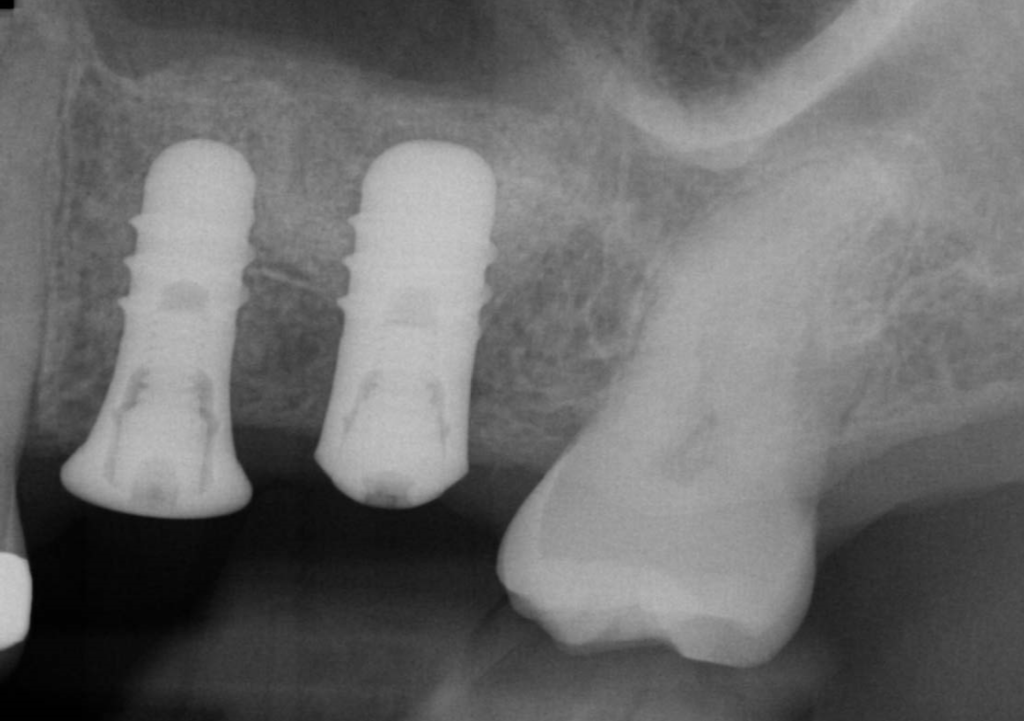

These implants were then restored with a screw retained PFM two unit bridge, abutment screws were torqued to 35Ncm, and access cavities were restored with PTFE tape and composite resin. Radiographs below shows excellent bone levels at one-year review.